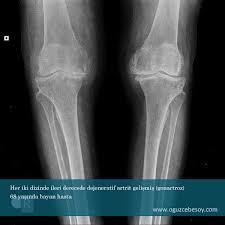

bel fıtığı yandan görünüm bel fıtığı üstten görünüm DİZLERDE ARTROZ